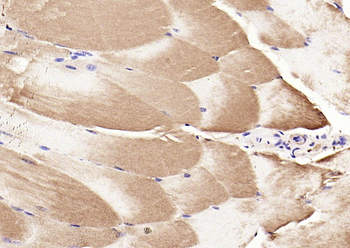

FC, IF, IHC-Fr, IHC-P, WB

应用稀释比例:WB=1:500-2000, IHC-P=1:100-500, IHC-F=1:100-500, IF=1:100-500, Flow-Cyt=1μg/Test